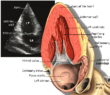

| Each figure contains a TTE with a black background, and a corresponding colored illustration. | Patrick J. Lynch and C. Carl Jaffe, Yale University, 2006. | ||||||||||

| Click on a figure to enlarge it and see some parts of the heart identified. RV, right ventricle; LV, left ventricle; RA, right atrium; LA, left atrium; TV, tricuspid valve; MV, mitral valve; AV, aortic valve; RVOT, right ventricular outflow tract; LVOT, left ventricular outflow tract | |||||||||||